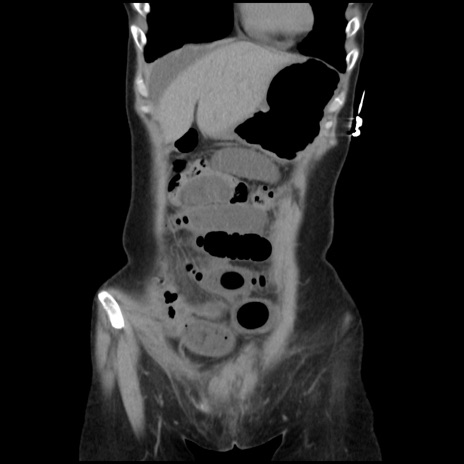

横断像